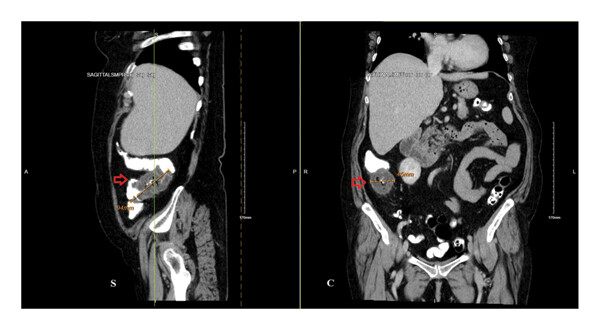

Физикальный осмотр и первичные лабораторные анализы не показали отклонений. Пациентке была оказана помощь при рвоте и отменен прием ибупрофена. КТ брюшной полости выявила в восходящем отделе ободочной кишки образование примерно 94×45 мм, что вызвало опасения по поводу аденокарциномы толстой кишки (рис. 1).

Рисунок 1. КТ с КУ брюшной полости выявило кольцевидное образование в проксимальном отделе восходящего отдела ободочной кишки (красные стрелки) длиной 94 мм и диаметром 45 мм, с нависающими краями и незначительным уплотнением околоободочной жировой ткани. Рядом отмечены множественные лимфатические узлы размером менее сантиметра (отсутствуют на представленных изображениях)..